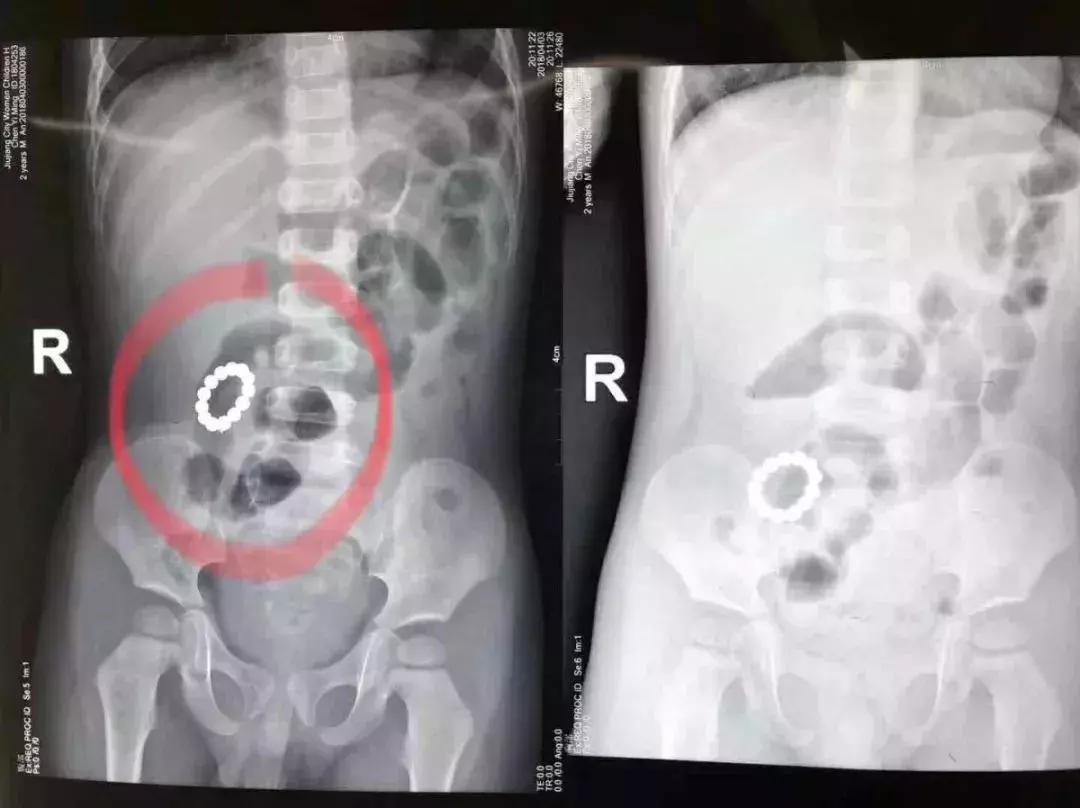

2岁的君君肚子疼,妈妈本以为是他吃坏了东西或着了凉,却猛然发现桌上的巴克球缺了一块,赶紧带他到医院检查,竟在君君消化道中发现了12颗小磁珠。君君爸妈想着磁珠颗粒不大又溜圆,可以自己排出来,可等了11天依然不见踪影,君君反而出现腹痛、呕吐、高热不断。

爸妈赶紧把孩子送到医院,检查发现,磁珠已经从胃里下降到结肠,并互相吸穿成了一个“手链”。专家会诊后决定行腹腔镜探查,术中医生发现,君君肠道内的磁石已随肠道蠕动,游走到不同地方的肠壁,且互相吸引已致肠道四处穿孔,腹腔镜也无法发挥作用。最终,12颗磁珠被开腹取出。